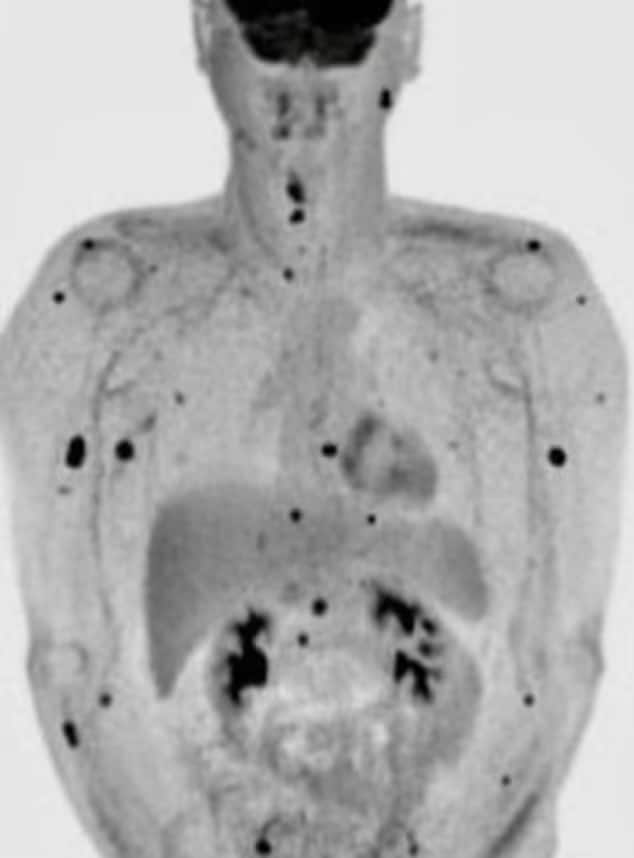

Os resultados mostraram que a protuberância era um melanoma nodular que se espalhou por seus gânglios linfáticos.

Uma segunda biópsia mostrou que ele estava com metástases e não podia mais esperar que os tratamentos o levassem à cura. Em agosto, os médicos lhe deram seis meses de vida.